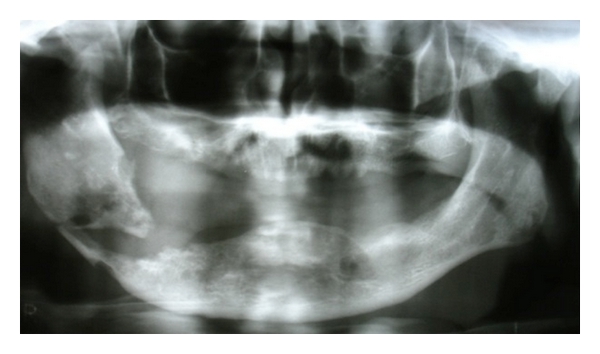

Case 3. A 51-year-old female was referred for evaluation of a submental fistula with purulent drainage, with evolution of 7 days (Figure 5(a)). Medical history revealed breast cancer and use of pamidronate (90 mg) for the past two years. Clinical exam showed absence of all teeth and normal mucosa. No radiographic changes were observed (Figure 5(b)). Based on clinical history and findings, the diagnostic hypothesis was BRONJ. The purulent material was collected and cultured, and revealed the presence of Staphylococcus epidermidis with sensitivity to clindamycin. Based on microbiological analysis, the patient was administered 300 mg oral clindamycin for 35 days, and the use of pamidronate was discontinued. Following this period, fistula closure was observed, along with absence of drainage. The patient is currently being followed up with no signs of recurrence.

(a)

(b)

Bisphosphonates are primarily effectively employed in neoplasia-related conditions, such as malignant hypercalcemia, bony metastasis, and lytic lesions of multiple myelomas [19]. Among bisphosphonates, zoledronic acid and pamidronate are most commonly employed. In addition, alendronate, risedronate, and ibandronate are frequently used for osteoporosis [20]. ONJ may occur due to enzymatic inhibition, which leads to cell toxicity induced by the medication. Patients that use intravenous bisphosphonates are more susceptible to BRONJ than those that take the medication orally. Systemic factors, such as diabetes, immunosuppression, and concomitant use of other drugs may also be involved with the development of BRONJ [21]. Most cases of BRONJ occur following extractions. Occasionally, BRONJ may spontaneously develop [22], such as in the current case. No oral infectious foci, exposed areas, or radiographic findings were present.